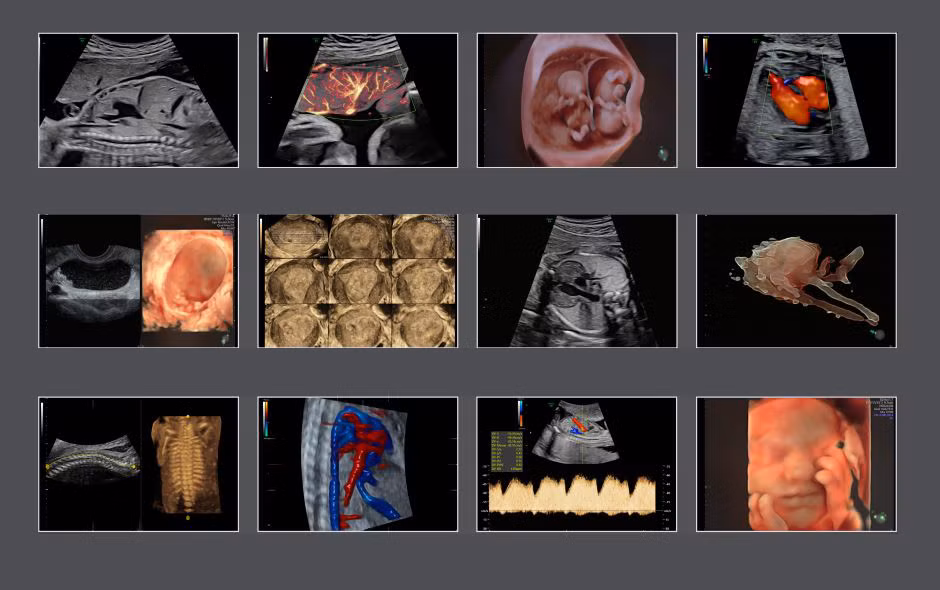

Thiết bị siêu âm 4D Voluson E8 là một trong những dòng máy siêu âm hiện đại nhất được sử dụng chủ yếu tại các bệnh viện lớn trên thế giới.

Công nghệ HDLive tích hợp trong dòng máy E8 cung cấp hình ảnh 4D có độ phân giải cao, biến động theo thời gian thực hỗ trợ đắc lực cho giải phẫu và theo dõi, đánh giá sự phát triển của thai nhi đặc biệt là phát hiện các dị tật phức tạp ngay từ giai đoạn sớm của thai kỳ.

Tính năng cải thiện hình ảnh cho phép quan sát chi tiết đến cả hệ thống tim mạch của thai nhi, tăng chất lượng kiểm tra tiếng vang, đánh giá các rối loạn nhịp tim và đo chức năng tim thai tốt hơn nhiều các dòng máy siêu âm thông thường.

|

| Hình ảnh siêu âm thai các tuần từ thiết bị Voluson E8 |